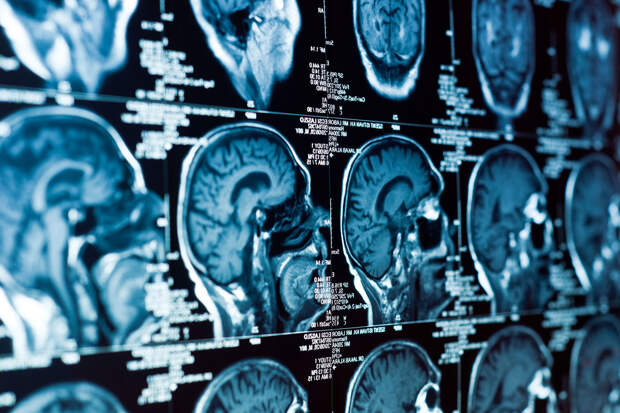

Ученые Колумбийского университета использовали звуковые волны для неинвазивного открытия гематоэнцефалического барьера — естественной "защиты" мозга, которая обычно препятствует попаданию лекарств в опухоли. Результаты исследования опубликованы в журнале Science Translational Medicine (STM).

Технологию в сочетании с химиотерапией протестировали на трех детях с диффузной срединной глиомой — редким и крайне агрессивным видом рака, который почти всегда приводит к летальному исходу.

Сфокусированный ультразвук позволил лекарственным препаратам успешно достичь опухолей, улучшая состояние пациентов без побочных эффектов."Теперь, когда мы убедились в безопасности метода у детей, можно проводить дальнейшие испытания с более высокими дозами препаратов для мозга на ранних стадиях болезни", — отмечает детский онколог и руководитель исследования Стергиос Захарулис, доцент Колумбийского университета.

Несмотря на успехи в лечении некоторых агрессивных опухолей, прогноз при раке мозга у детей остаётся крайне тяжелым: большинство пациентов с глиомой срединных структур живут менее года после постановки диагноза. Основная проблема — гематоэнцефалический барьер, который защищает мозг от токсинов и инфекций, но блокирует действие химиотерапию.